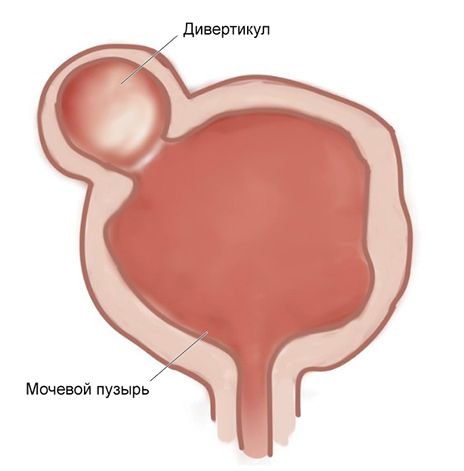

Дивертикул мочевого пузыря (Bladder diverticulum) — это выпячивание стенки пузыря, которое сообщается с ним небольшой шейкой. Патология часто протекает бессимптомно, но может проявляться задержкой мочеиспускания и кровью в моче.

Дивертикул мочевого пузыря